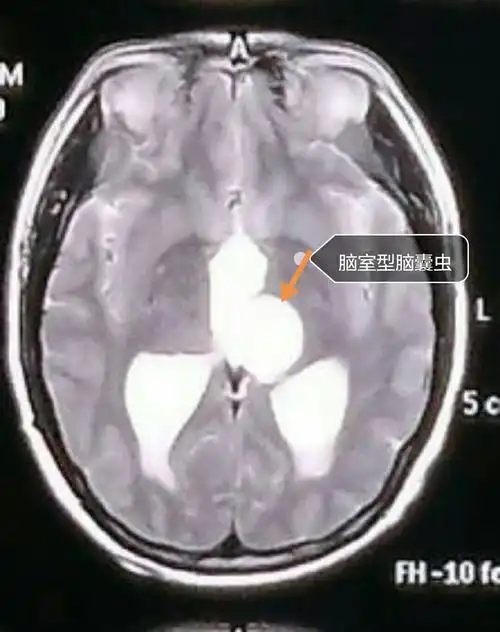

这可能会压迫脑组织,引起脑组织炎症,软化,水肿等.

脑囊虫也导致三叉神经痛!罕见